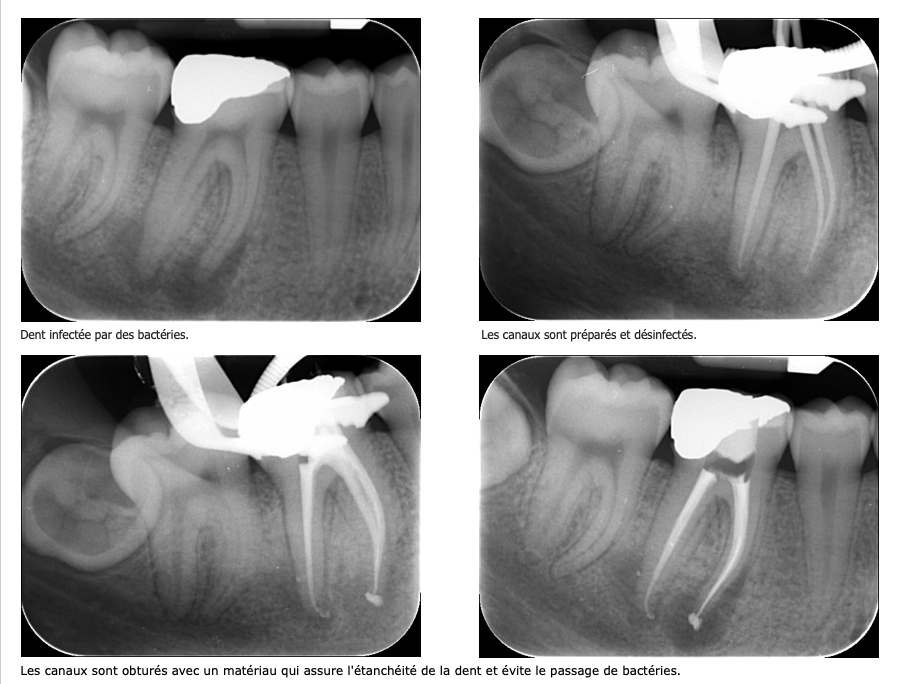

En présence d'une inflammation irréversible ou d'une infection , le chirurgien dentiste est amené à réaliser un traitement endodontique qui permet de supprimer l’ensemble des tissus infectés se trouvant dans les canaux radiculaires.

Au cours de ce traitement, l’ensemble des canaux sont nettoyés, désinfectés et enfin obturés afin d’éviter toute réinfection.

Ce traitement est réalisé sous anesthésie locale, comme n’importe quel soin. Le traitement endodontique permettra de désinfecter l’ensemble des canaux.